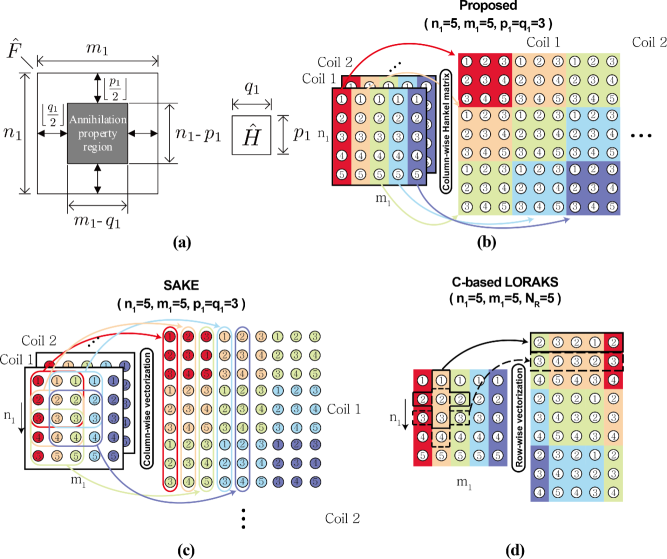

Similarly, we define annihilating filter matrix . Then, by removing the boundary effect from the 2D convolution as shown in Fig. 2(a), the 2D annihilation property should hold only inside of the domain and (82) can be equivalently represented as

where the overline denotes an operator that reserves the order of a vector. Using this, we can construct an augmented matrix in (66) from -channels.

The augmented matrix structure illustrated in Fig. 2(b) is similar to those of SAKE and LORAKS/P-LORAKS in Fig. 2(c) and (d), respectively, with the following differences. Compared to SAKE, ALOHA stacks the multi-coil Hankel matrices side by side. Unlike the SAKE and ALOHA, LORAKS uses (: neighborhood size) neighbors according to the software manual provided by the original authors. Moreover, the most important novelty of the proposed method is the k-space weighting to construct the Hankel structured matrix.